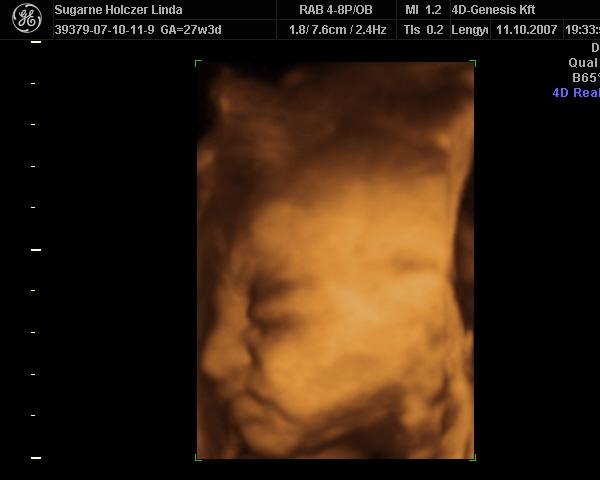

Ind, gyönyörű babád van

– köszi a képeket

Azt még megkérdezem, hogy ti most tulajdonképpen mennyi idősök vagytok? – a kép szerint 27hét+3nap, a vonalzód szerint pedig 26 hét.... – nagyobb a babád, mint kellene?